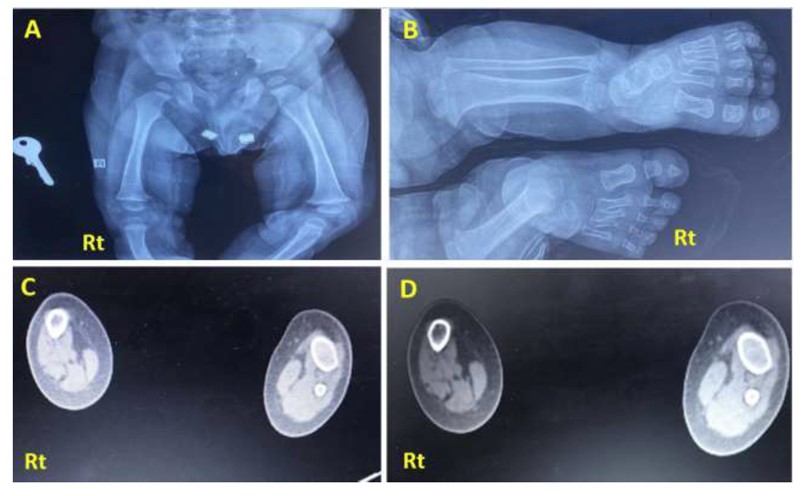

Imaging study, including X-rays (Figs. 2 and 3) and CT scans, confirmed the FH diagnosis and defined its severity. The case involved fibular hemimelia, characterized by fibular hypoplasia, a bowed tibia, and limb shortening, combined with proximal femoral focal deficiency (PFFD), in which the femur is shortened, angulated, or bowed, but demonstrates normal mineralization. PFFD tends to associate with FH in 50% of the cases [13, 14]. The ankle joint, foot, and tibia bone were unaffected. The diagnosis was consistent with type II FH with PFFD.

X-ray of the presented case. (A) Anteroposterior projection of both legs showing a completely absent Rt fibula with limb shortening and limb length discrepancy compared to the Lt side. The tibia is foreshortened, thickened, and bowed with medial rotation. (B) X-ray frontal view of Rt and Lt femur showing underdeveloped Rt femoral head compared to the Lt side, consistent with mild Rt proximal femur deficiency. (C, D): CT scan of both legs (axial section view) showing absent Rt fibula with deficiencies of the related muscular component, with the Rt tibia showing reduced radius compared to the Lt side.